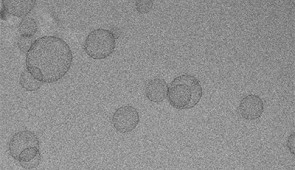

To develop a more effective delivery system, Mirkin and his team turned to SNAs. Invented and developed by Mirkin at Northwestern, SNAs are globular nanostructures with a nanoparticle core surrounded by a dense shell of DNA or RNA. In previous studies, Mirkin discovered that cells recognize SNAs and invite them inside. In the new study, his team built new SNAs with the chemotherapy chemically incorporated into the DNA strands.

SNAs under a cryogenic electron microscope.